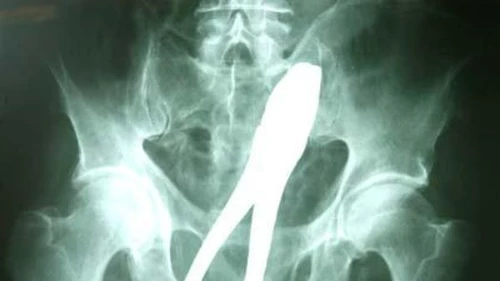

En circunstancias que se desconocen, un poblador del Municipio de Challapata, en Bolivia,  concurrió al hospital general “San Juan de Dios” de Oruro  con síntomas de molestias graves, las cuales se descubrió que eran causadas por un alicate que tenía alojado en el recto y que obligó a que sea intervenido quirúrgicamente de urgencia.

Si bien no trascendió el nombre, se trata de un ciudadano de sexo masculino de aproximadamente 48 años de edad, quien fue intervenido ante la sorpresa del personal médico por los resultados del examen radiológico al que fue sometido, para establecer la posición del cuerpo extraño que tenía en su organismo.

Cuando el personal de guardia, mirando las radiografías, observó que la persona mayor tenía incrustado en el recto un alicate mecánico, sin poder explicar la víctima las circunstancias en que le ocurrió el fenómeno, la intervención fue la única opción posible.